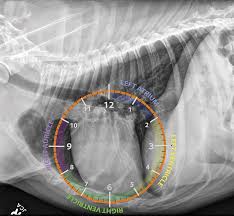

Esami di approfondimento

Nei casi positivi o sospetti possono essere indicati:

• radiografie toraciche

• ecocardiografia

• esami ematochimici

Questi esami aiutano a valutare la gravità della malattia e a pianificare il trattamento più sicuro.